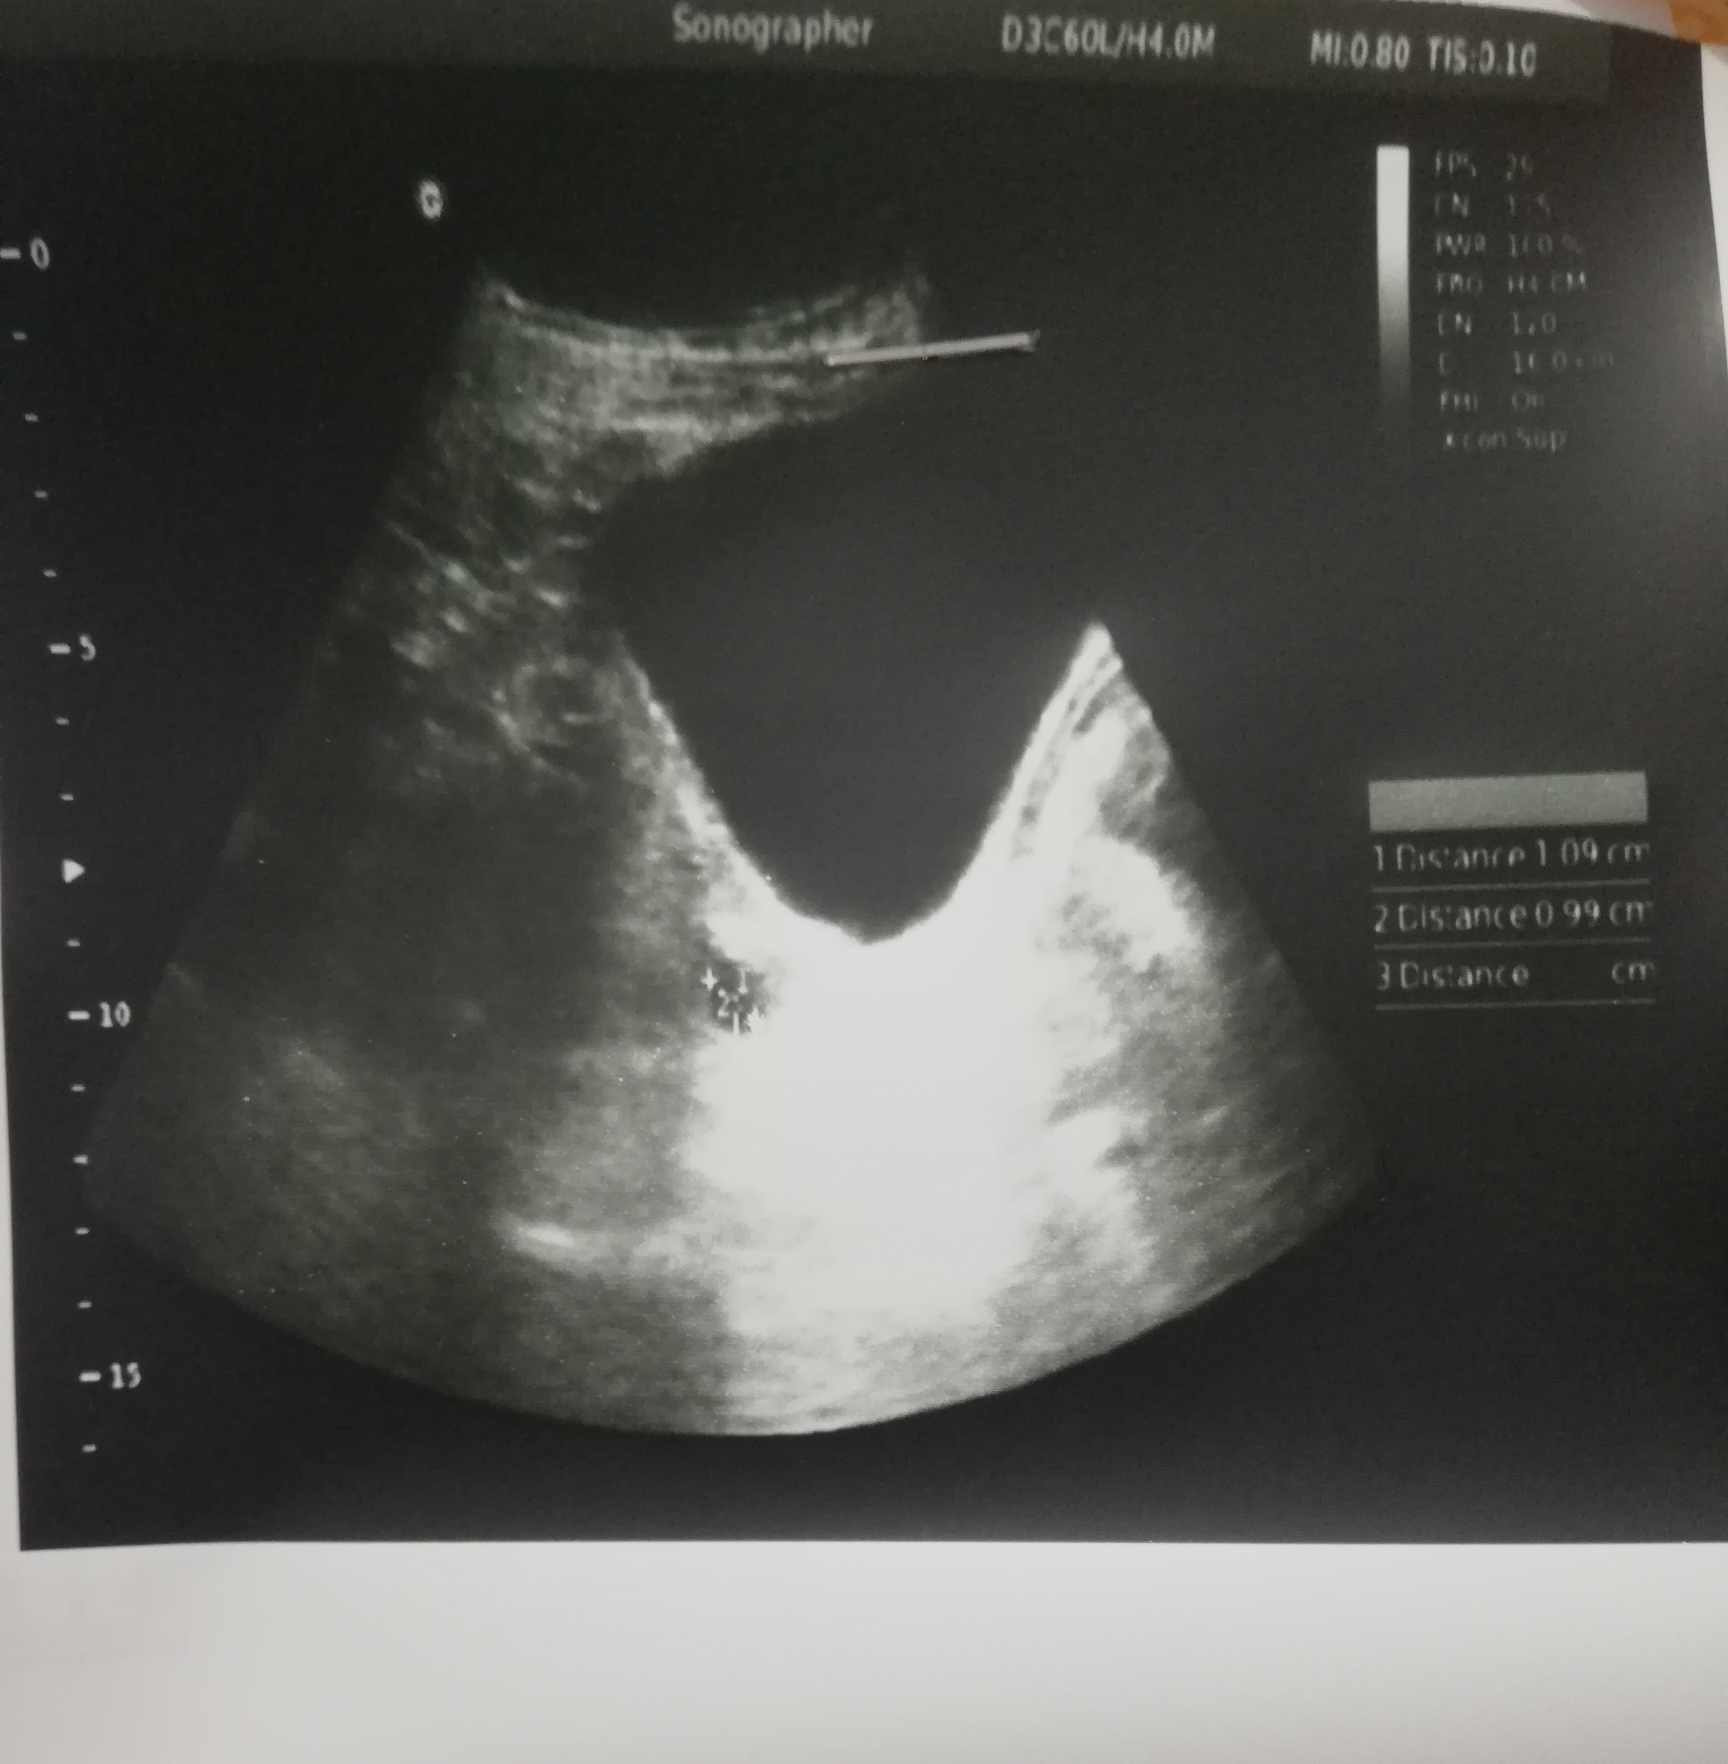

History of one miscarriage at week 5 in April 2022. Now trying to conceive again also I have 1 daughter of age 7. This is the ultrasound report on periods 12th day. Doctor plz guide.

ji dominant follicle of 1cm seen .u need more medicine plz consult me online by clicking my profile or in clinic

follicle size os not ideal for conception.